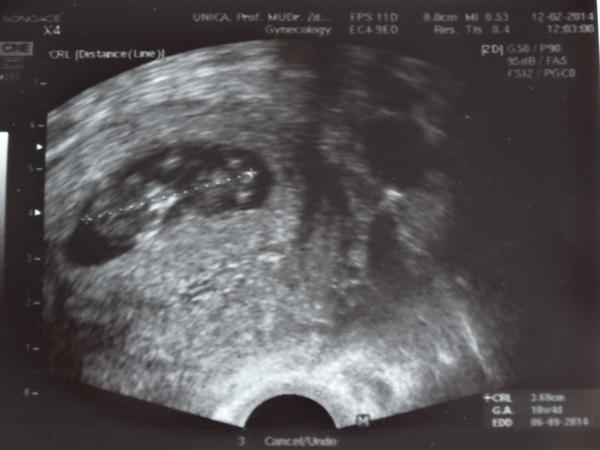

holky tohle je druh zvaný Mimino Obecné 😀 dnešek dopadl dobře......jsme 10+4, takže 11 tt. a screening bude za tři týdny 😉 nemám komu ukázat fotečku, všichni jsou v práci, tak aspoň Vám 🙂 vlevo to velký kulatý je hlava 😀 😀